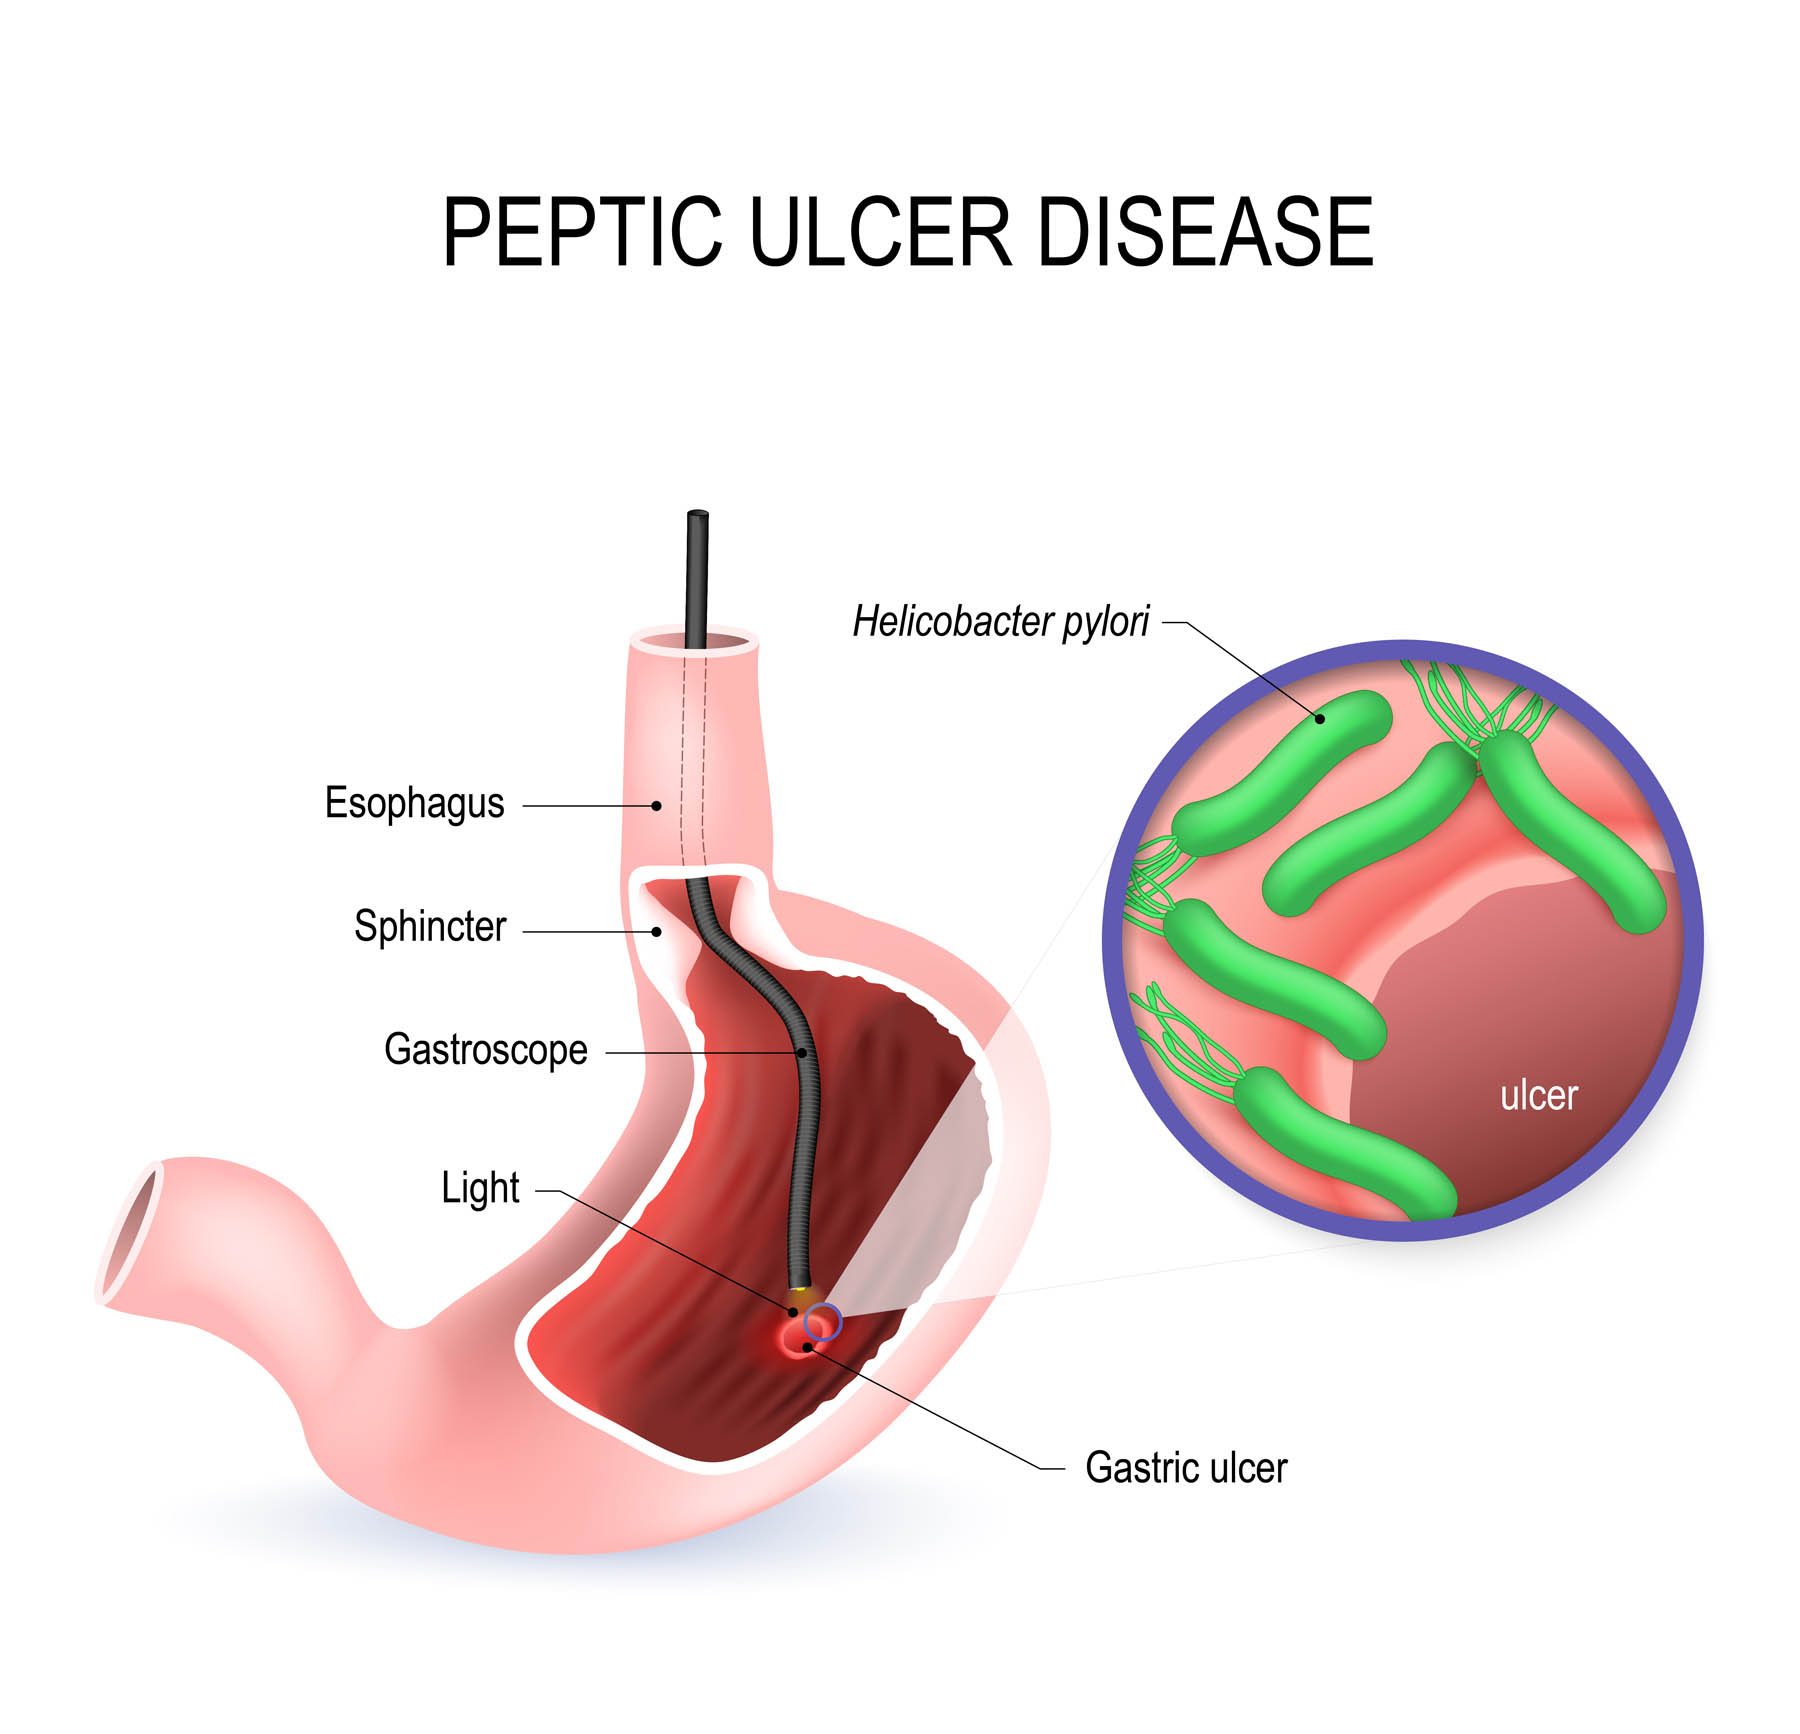

Gastric Cancer, Acid Reflux, Helicobacter Infection | HK Surgeon

Do ulcers hurt when you push on your stomach: Stomach Cancer vs …